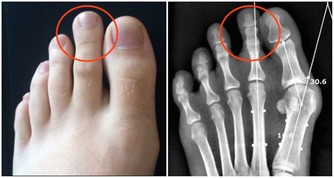

■ 出汗好處3/防治肢體性疾病

其實,「生汗」不僅能排出血液裡的廢物垃圾,稍微增加一點運動量,活動到出汗,還能防治肢體性疾病,如常見的關節炎、關節痠麻沉重、肌肉痛、四肢痙攣等。

有人可能要問,肢體有病還運動,不是往傷口上撒鹽嗎?為什麼運動還能防治關節疾病呢?痛則不通,通則不痛。從中醫角度來講,所有的疼痛疾病,都是由於外邪入侵或身體內部失調,導致氣血淤滯所引發,治療的原則就是疏通經絡,促進氣血流通,而適當的運動,正是疏經活血的最好辦法。